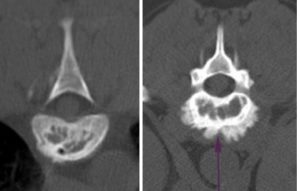

A gerincoszlopról készült röntgenfelvétel már kiindulási pont lehet, azonban korai szakaszban lehet negatív röntgenlelet. A betegség előrehaladtával a csigolyatest szerkezete elkezd felbomlani mely röntgenfelvételen is látványos lehet. A teljes gerinc (csigolyák, a porckorong és a gerincvelő) pontosabb leképzéséhez és az elváltozás pontos helyének meghatározásához CT vagy MRI vizsgálat szükséges. További kiegészítő laborokra is szükség van: vérkép, biokémiai vérvizsgálat, vizeletvizsgálat, esetleg szerológiai vizsgálat a kórokozók pontos meghatározására.

Az alábbi CT felvételen deformált, szerkezetében bomlott csigolyatest jól látható.